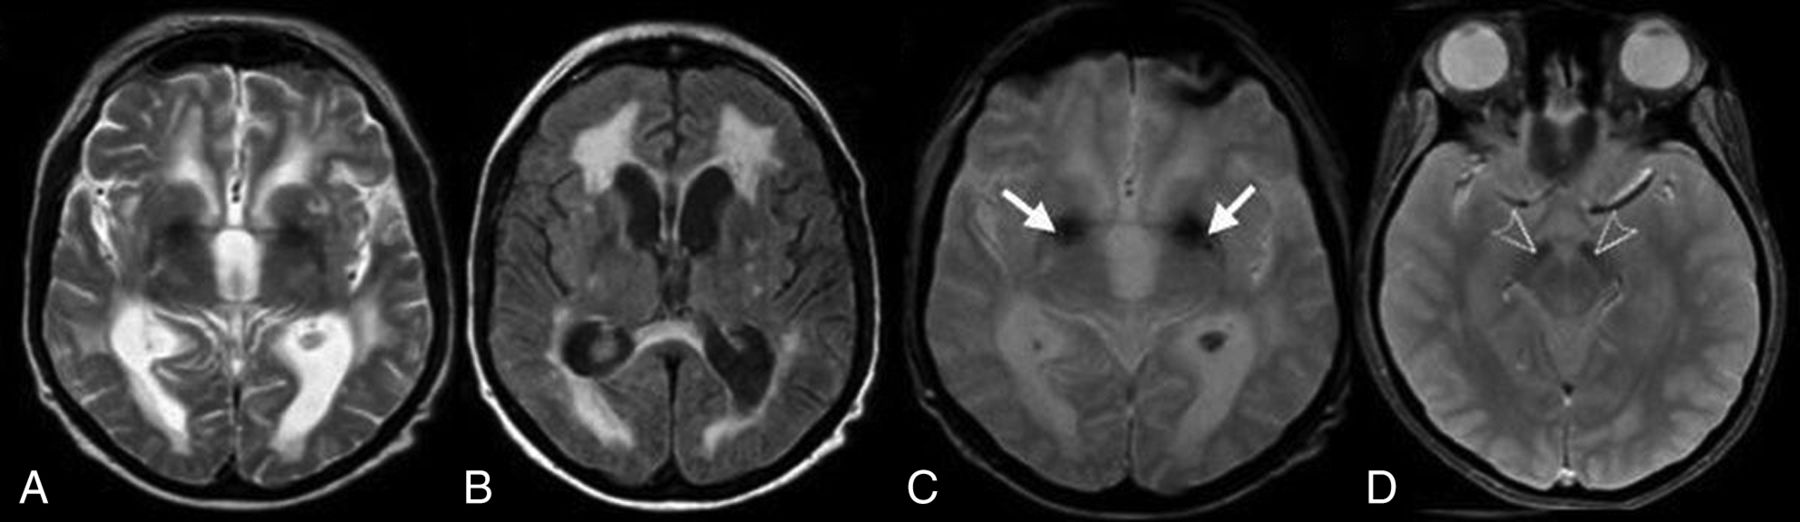

Evidence of iron deposition in the globus pallidus was observed in 19 patients (73%) (Fig 2A–C). Involvement of the substantia nigra and red nucleus was noted in 6 patients (23%) (Fig 2D). MR spectroscopy in 4 patients demonstrated normal major metabolite peaks. Despite the clinical finding of generalized or focal dystonia, 3 patients showed no evidence of iron deposition on MR imaging.

Axial T2-weighted (A), FLAIR (B), and T2* (C) MR images in case 11 show putaminal blooming artifacts (arrows) reflecting iron accumulation. An axial T2* MR image (D) in case 3 shows iron deposition in the substantia nigra (arrowheads).

White matter abnormalities on T2-weighted and FLAIR images were seen in 18 patients (69.2%). These changes varied in terms of distribution and extension (Fig 3). Extension of WM changes was characterized by a periventricular and frontoparietal predominance (Fig 4A, -B). Involvement of other subcortical (basal ganglia, thalamus) and infratentorial structures was seen in 3 patients (11.5%) (Fig 4C, -D). Older age was associated with more severe white matter lesions (r = 0.71, P < .001). All white matter lesions were nonenhancing and spared the U-fibers.

Axial (A) and coronal (B) FLAIR MR images for case 24 show white matter changes with frontal predominance (arrows). Axial FLAIR images show signal intensities (arrows) involving the pons (C) in patient 19 and the cerebellum (D) in patient 26.